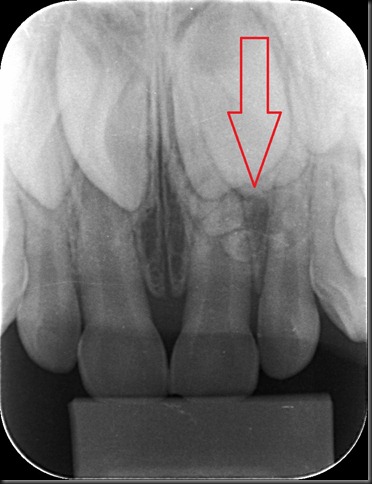

| Radiografias panorâmica e periapical pré-cirúrgicas (CIR - Centro da Imagem Radiográfica) |

| Radiografias panorâmica e periapical pré-cirúrgicas (CIR - Centro da Imagem Radiográfica) |